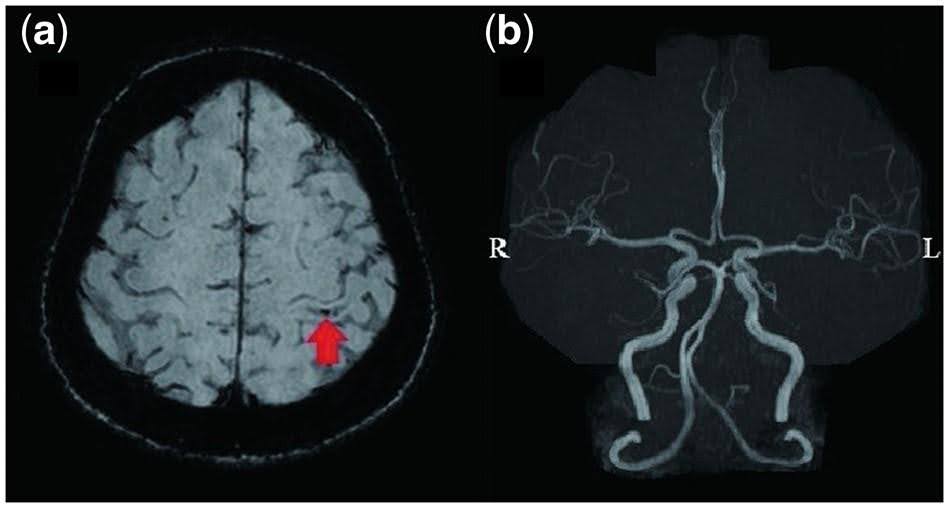

Vaskuläre Veränderungen scheinen bei einigen Patienten mit einer SARS-CoV-2-Infektion in unterschiedlichen Formen aufzutreten. Neben einer Hypoperfusion und Hyperpermeabilität kleinerer Gefäße können auch Thrombosen auftreten. Im Rahmen einer SARS-CoV-2-Infektion kann es zu makro- und auch zu mikrovaskulären Thrombosen kommen. In Fallberichten wurden ausgedehnte mikrovaskuläre Thrombosen beschrieben. Eine thrombotische Mikroangiopathie könnte eine Mitursache für die thrombotischen und multiorganischen Komplikationen von COVID-19 sein.5 Am 15. Juni dieses Jahres wurde ein interessanter Fallbericht zu dieser Thematik veröffentlicht. Bei einer 56-jährigen Patientin mit schwerer COVID-19-Erkrankung und zerebraler Mikroangiopathie zeigten sich keine offensichtlichen Anomalien im MRT (siehe Abbildung 1). Dies erschien Ymoto W. äußerst ungewöhnlich. Imoto W. zufolge kann es sich in so einem Fall um eine durch COVID-19 ausgelöste Mikroangiopathie handeln.5

Abbildung 1:

Magnetresonanztomographie des Schädels. (a) Empfindlichkeitsgewichtete Magnetresonanztomographie des Gehirns: Ein kleiner Bereich mit Mikroangiopathie im Gyrus postcentralis ist erkennbar (roter Pfeil); (b) Magnetresonanzangiographie, die keine offensichtlichen Anomalien zeigt.5